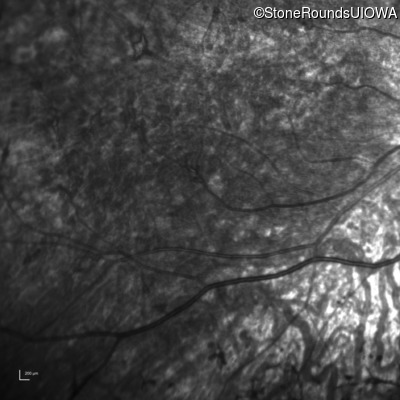

Infrared Fundus Photograph - Left - 5/180

Exemplar